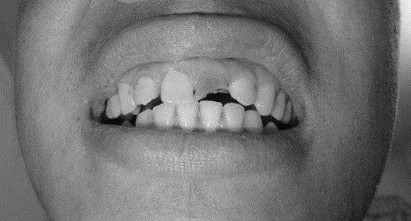

1、患者,男,38歲。上前牙變色1年,自述上前牙5年前受過外傷,唇側(cè)傾斜,檢查可見左上1牙冠變色,牙冠缺損近1/2,牙髓測(cè)試無反應(yīng),X線根尖片顯示患牙無明顯異常,全景片顯示雙側(cè)下頜智齒近中阻生,之前有發(fā)炎化膿病史,目前無咀嚼不適??谇黄溆酂o異常。

檢查情況及X線片見下圖:

(1)主訴診斷:左上1牙髓壞死(外傷)